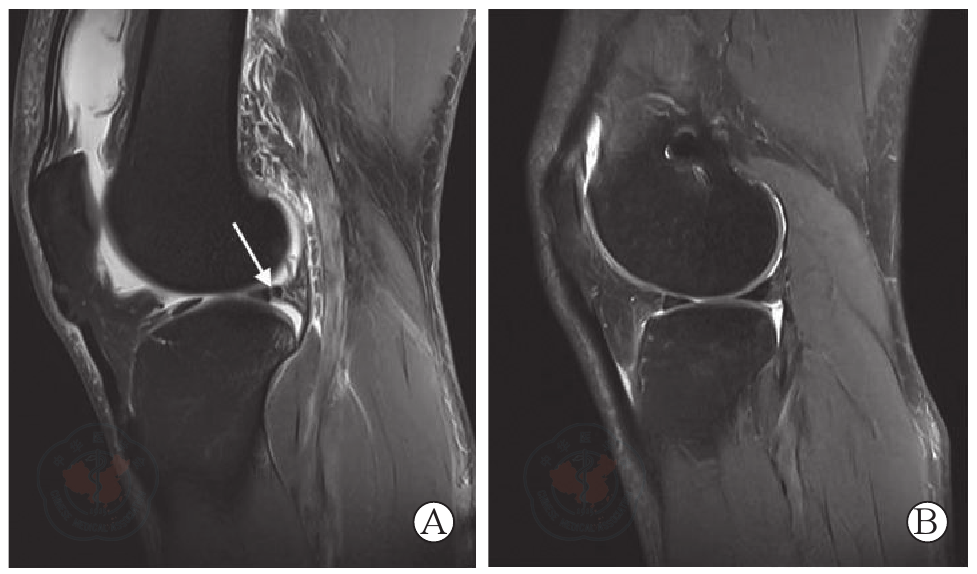

图2 外侧半月板后根撕裂修复手术前后膝关节MRI。图A为术前MRI(矢状位)显示外侧半月板后根撕裂(箭头示撕裂处高信号);图B为术后12个月MRI显示撕裂处信号连续,半月板结构修复良好

Figure 2 MRI images of knee before and after repair surgery for posterior root tear of the lateral meniscus. A is MRI (sagittal view) before surgey showing a posterior root tear of the lateral meniscus (arrow indicates the high signal at the tear site); B is MRI at 12 months after surgery, showing continuous signal at the tear site and good repair of the meniscus structure